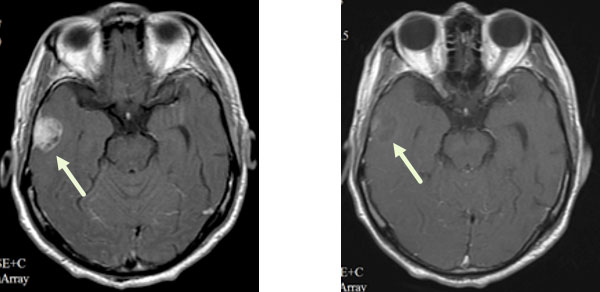

(1)

放疗前 放疗后